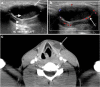

Focal and diffuse thyroid abnormalities are commonly encountered during the interpretation of computed tomography (CT) exams performed for various clinical purposes. These findings can often lead to a diagnostic dilemma, as the CT reflects the nonspecific appearances. Ultrasound (US) examination has a superior spatial resolution and is considered the modality of choice for thyroid evaluation. Nevertheless, CT detects incidental thyroid nodules (ITNs) and plays an important role in the evaluation of thyroid cancer. In this pictorial review, we cover a wide spectrum of common and uncommon, incidental and non-incidental thyroid findings from CT scans. We also discuss the most common incidental thyroid findings, best practices for their evaluation, and recommendations for their management. In addition, we explore the role of imaging in the assessment of thyroid carcinoma (before and after treatment) and preoperative thyroid goiter, as well as localization of ectopic and congenital thyroid tissue.

Teaching points: • Thyroid disorders tend to have non-specific CT appearances. • ITNs are common on neck CT. • ITN management depends on nodule size, age, health status, lymphadenopathy, and invasion. • CT is used in assessment of cancer extension, mass effect, invasion, and recurrence. • CT plays a role in preoperative planning in patients with symptomatic goiter.